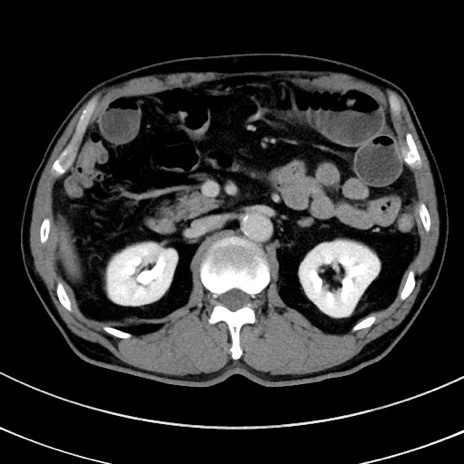

症例8(横断像)

【症例】 60歳代男性

【主訴】 黒色吐物

【現病歴】 4日前から嘔気自覚、2日前の朝食後にも嘔気あり、自分で手で嘔吐反射起こし嘔吐したところ血が混ざっていたため受診。

【既往歴】 5年前汎発性腹膜炎を伴う急性虫垂炎で手術、高血圧、前立腺肥大症、高脂血症

【身体所見】 腹部正中に手術癩痕あり 腹部平坦・軟圧痛なし膨満感あり

【データ】WBC 8400、CRP 4.54